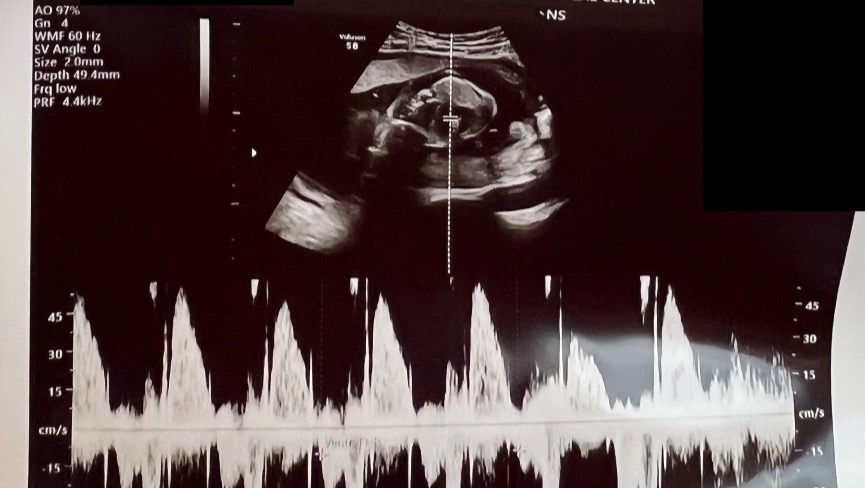

My baby sister, Emily and husband, Cody Pettis, are expecting their second baby girl, Emma Kate, due in July.

Their sweet girl has been diagnosed with Hypoplastic Right Heart Syndrome (HRHS) and will require several heart surgeries, the first being immediately after she is born. Her most recent appointment with the Neonatal Cardiac Surgeon has shown even further complications potentially requiring a heart transplant.